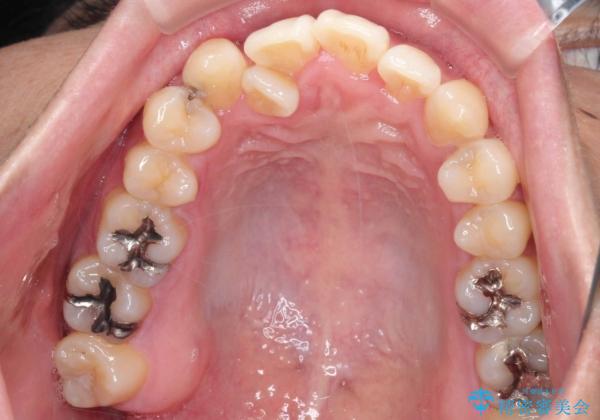

- 「歯のデコボコと前歯が引っ込んでいるのを治したい」を主訴に来院された患者様です。

デコボコの量が多かったため上下左右4を抜歯してワイヤー矯正で治療を行いました。

正面から見たときに右上2が全く見えないくらい、右上2が後ろに引っ込んでいる状態でしたが綺麗に並べる事が出来ました。